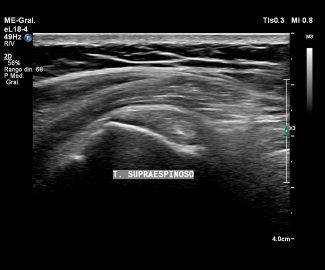

Especialista en diagnóstico por imágenes con más de 25 años de experiencia en el campo del ultrasonido y radiología digital. Trabajamos con equipos de alta tecnología garantizando la calidad y seguridad de nuestros diagnósticos, pues nuestra prioridad es la salud, bienestar y satisfacción de nuestros pacientes.

Sabemos que visitar un centro médico a veces genera nervios. Por eso, hemos creado un ambiente cálido, moderno y 100% seguro para ti. Desde nuestra cómoda sala de espera hasta nuestras áreas de ecografía, mamografía y rayos X, cada rincón está equipado con tecnología de última generación y diseñado para que te sientas en confianza.